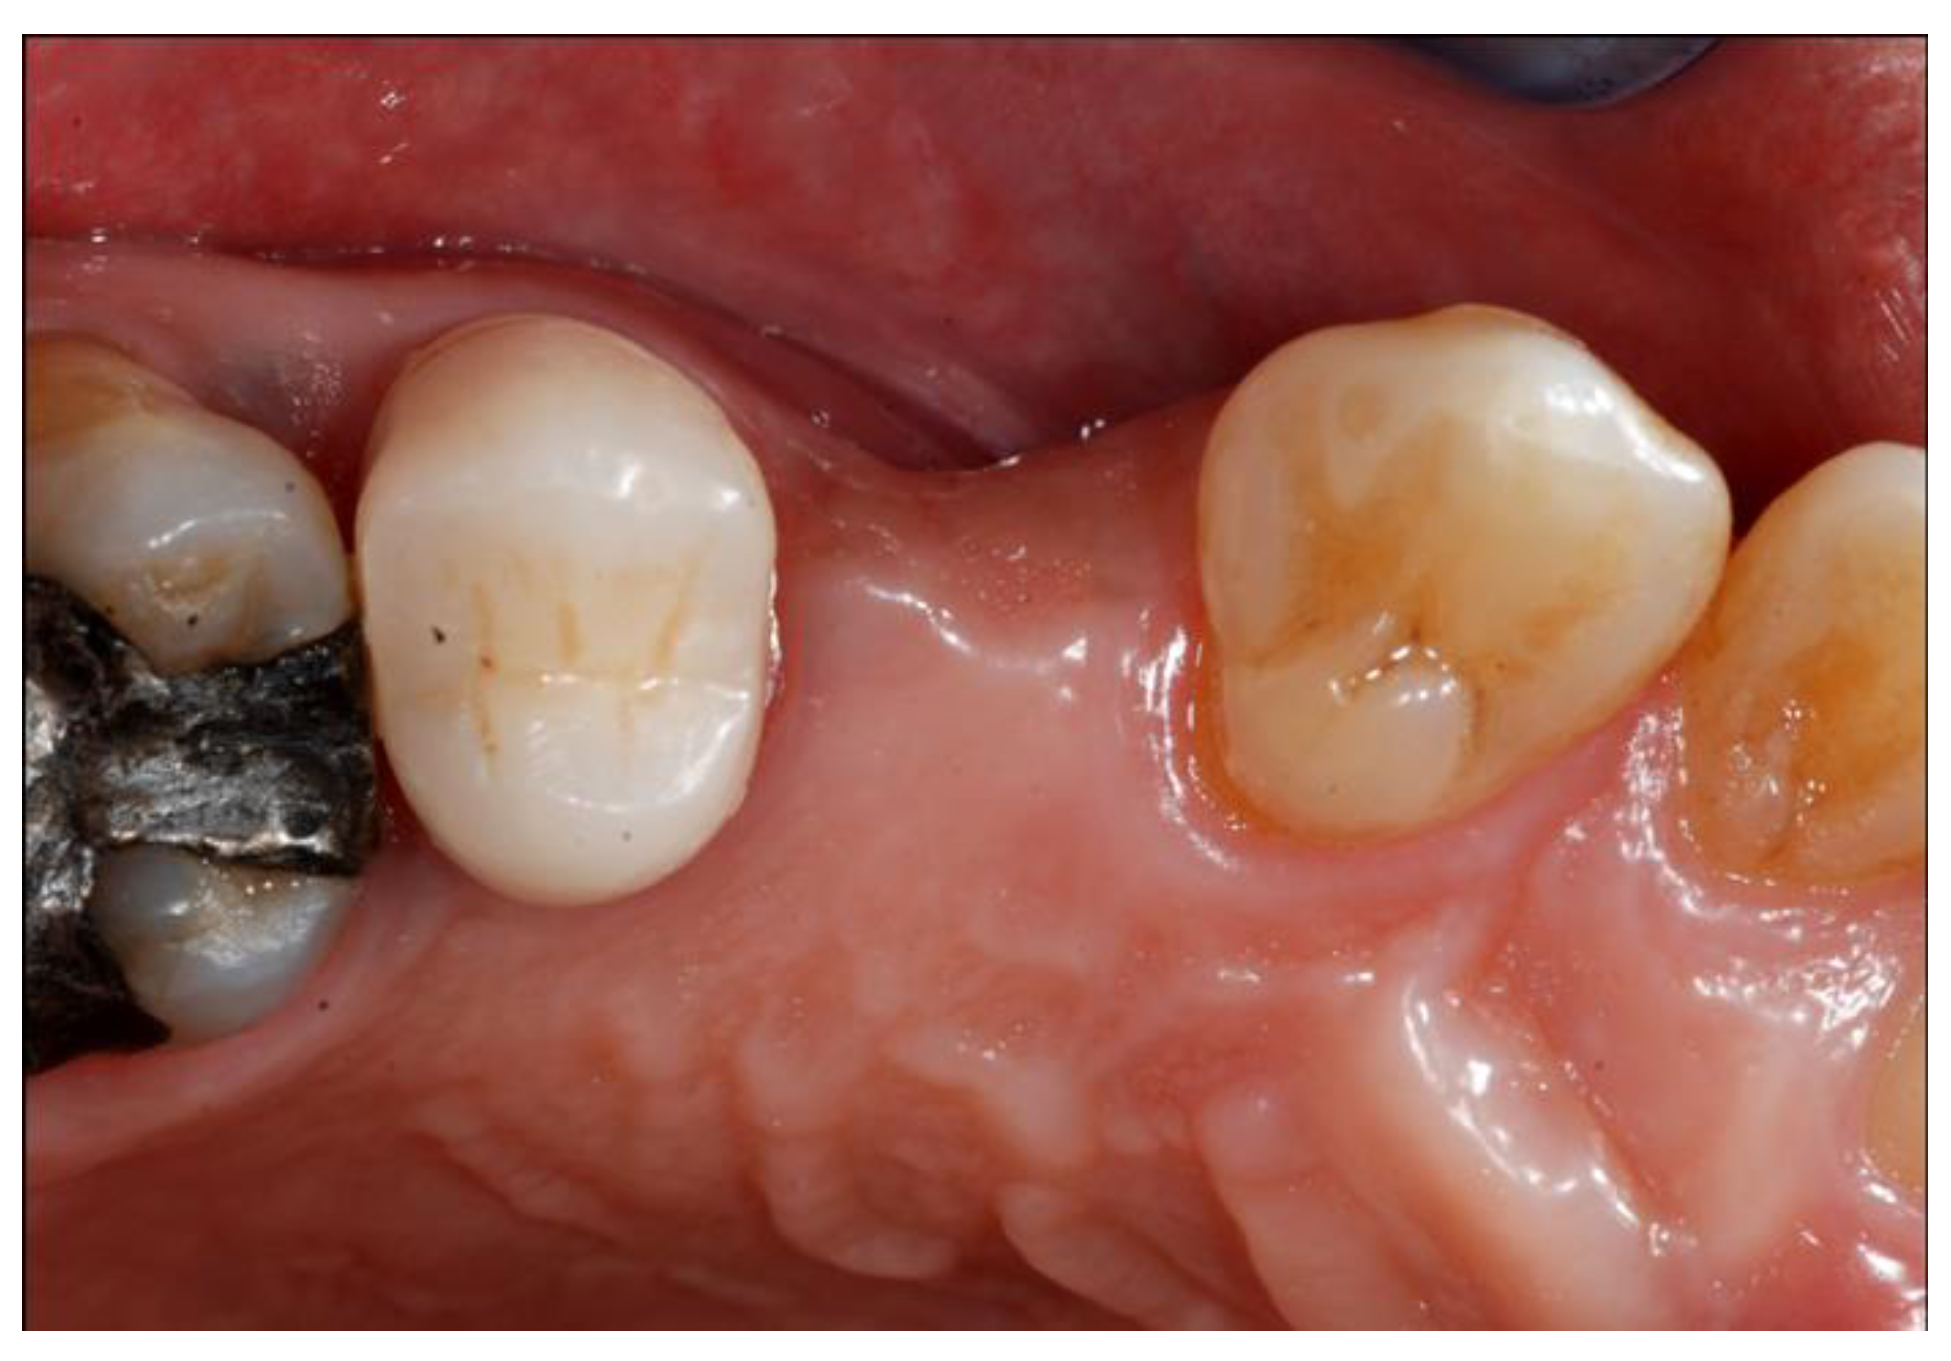

2.4. Surgical Phases

2.5. Re-Entry Surgery and Prosthetic Phases